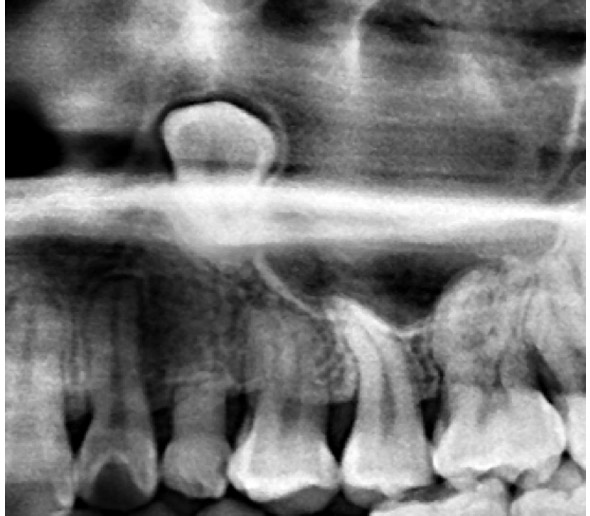

(兩條紅線中間黑色區域即為神經管)

外面拔完時常術後唇麻舌麻,本院發生趨近於零